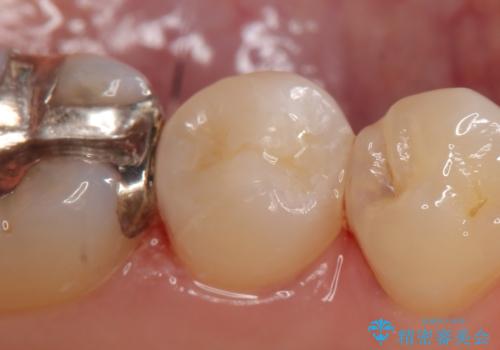

セラミックインレー 他院にて歯の神経治療が必要と言われた虫歯

- 他院にて左下5の虫歯治療を行おうとしたところ、歯の神経治療をすると言われたため、できれば神経を残せないかと当院にいらっしゃった方の症例です。

自発痛・持続痛等の症状がなく、露髄(歯の神経が露出してしまうこと)することなく虫歯の除去を完了したため、しばらく経過観察を行った後に神経治療をすることなく、セラミックインレーによる修復を行うことができました。